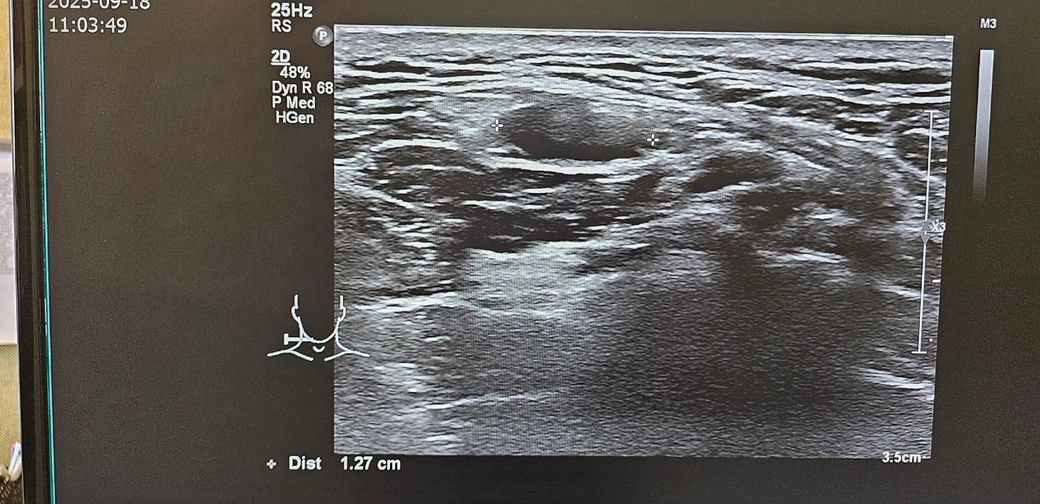

경부 초음파찍었는데 초음파 사진좀 봐주세요.. .

목통증이 있어서 초음파를 했는데

여러개가 부어있다고 하셨습니다

• 2번 째 사진

초음파 소견으로는 림프절들이 보이며 부어 있다 정도로 보입니다. 이외에 특별하나 소견이 따로 있거나 해 보이지 않습니다. 약물 치료를 하여도 회복이 되지 않다면 추가적으로 약물 복용을 해주며 경과를 지켜보거나 보다 정밀 검사를 통해서 다른 문제는 없는지 감별해보는 방향이 있겠습니다. 이비인후과적으로 재차 상담을 받아보시는 것을 권고드립니다.